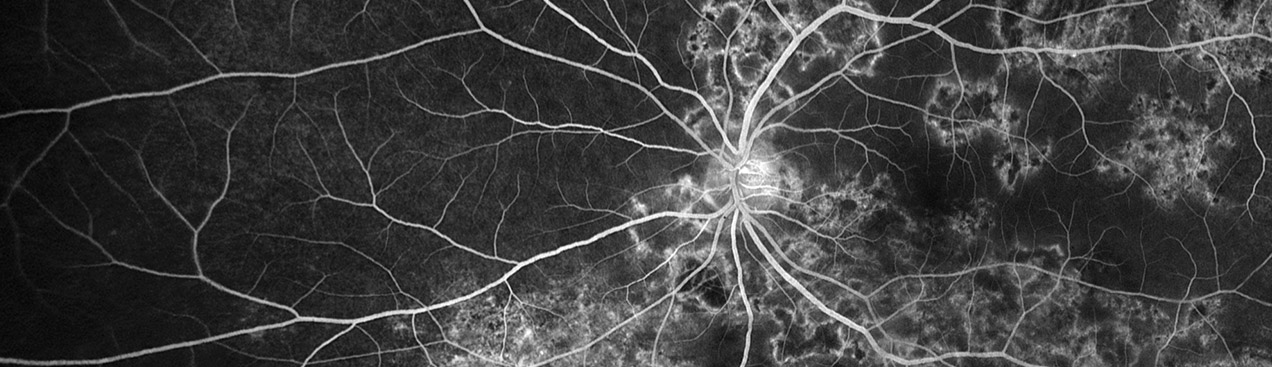

Uveitis is inflammation of the uveal tract which can be caused by autoimmune disorders such as rheumatoid arthritis or infection which can be idiopathic. The uvea is responsible for the transport of blood including inflammatory cells and is critical for vision. It can occur at any age and can result from many causes including systemic disease. Uveitis can be categorized as anterior, intermediate and posterior. Posterior uveitis can cause damage to the optic nerve, abnormally high pressure in the eye, cataracts or an accumulation of fluid within the retina which may cause retinal detachment. The clinical studies and articles below can assist in the identification of uveitis using Optos technology and further validate the use of 200 degree, single-capture optomap ultra-widefield retinal imaging for the detection, management and treatment of Uveitic eye disease.

Optos offers multimodal imaging with all ultra-widefield devices. Having both ultra-widefield and four images captured in less than one second has been shown to enhance pathology detection and disease management as well as improve practice and clinic flow. Ultra-widefield multimodal imaging is important across all access points of patient care - screening, detection, diagnosis, and treatment.